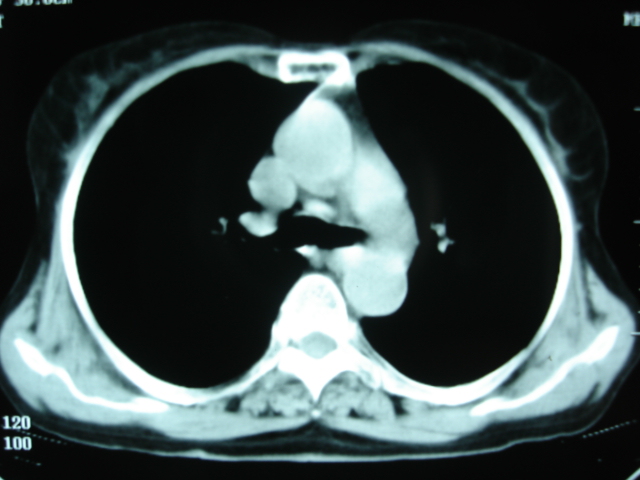

以下是引用卜一在2009-9-7 19:51:00的发言:[br][br] 1 左侧胸内甲状腺占位-多考虑甲状腺腺瘤! 2、左肺门占位-建议增强扫描以便明确性质。 3 慢支并感染! [br]

以下是引用shibing在2009-9-7 20:40:00的发言:[br]左侧胸内甲状腺占位-多考虑甲状腺腺瘤! 2、左肺门占位-建议增强扫描以便明确性质。 3 慢支并感染! [br]